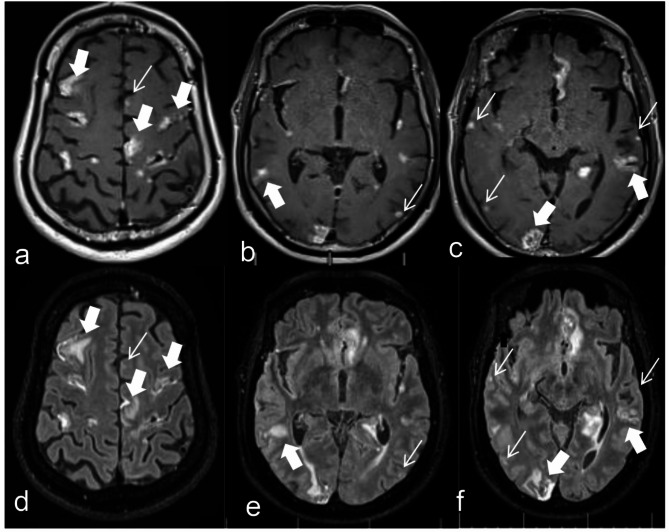

Objective: To investigate the diagnostic value of CE-MATRIX-T1FLAIR and 3D CE-T2FLAIR sequences based on Contrast Enhancement Modulated flip Angle Technique in Refocused Imaging with eXtended echo train (CE-MATRIX) technology for detecting Leptomeningeal Metastasis (LM) using Fluid Attenuated Inversion Recovery (FLAIR) imaging.

Methods: This prospective study included 563 hospitalized patients with clinically suspected LM, diagnosed with malignant tumors between January 2022 and October 2023 at Henan Cancer Hospital. Both CE-MATRIX-T1FLAIR and 3D CE-T2FLAIR sequences were used for imaging. Two radiologists independently evaluated image quality, diagnostic confidence, and objective measurements, diagnosing LM as positive or negative, with disagreements resolved by consultation. Subjective and objective scores were compared using the Wilcoxon signed-rank test. The diagnostic performance of the sequences was compared using ROC curve analysis, with cerebrospinal fluid (CSF) cytology as the gold standard. Sensitivity, specificity, positive predictive value (PPV), negative predictive value (NPV), accuracy, and area under the curve (AUC) values were calculated and compared using Z-tests.

Results: LM was confirmed in 321 patients. CE-MATRIX-T1FLAIR showed superior subjective scores in image quality and diagnostic confidence (p < 0.001). Though CE-MATRIX-T1FLAIR had a lower SNR (p = 0.013), it demonstrated higher sensitivity, specificity, PPV, NPV, accuracy, and AUC than 3D CE-T2FLAIR (p < 0.001). Both sequences provided effective diagnosis and differentiation of LM.

Conclusion: CE-MATRIX-T1FLAIR offers superior diagnostic performance compared to 3D CE-T2FLAIR for LM, with slightly better subjective ratings despite a lower SNR. Both sequences are effective for diagnosing LM.